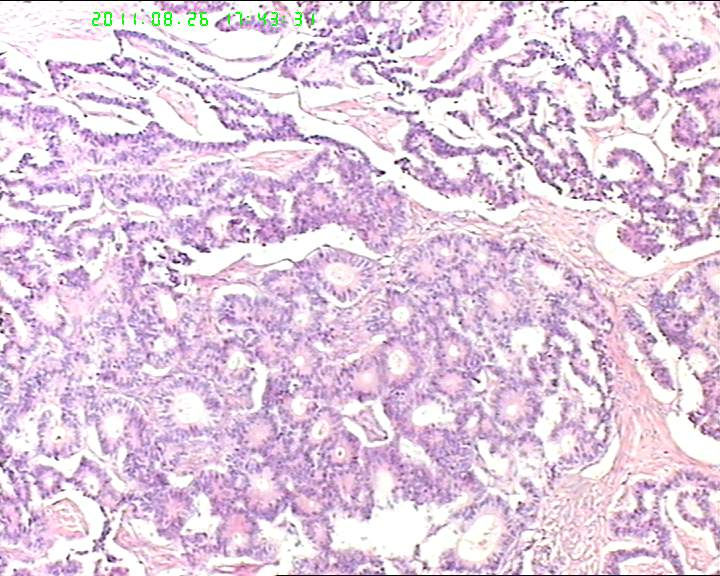

76岁女性卵巢巨大囊性肿物

卵巢肿物,大小18*14*10cm

,切面灰黄色,中央见一囊腔,12*4cm大小,未见内容物,内壁光滑。囊壁厚约4cm。

此3张图片为宫颈处组织

本例瘤细胞虽排列呈菊形团或腺管样,但瘤细胞核内未见核沟,核的形态也不是典型的石榴子样,故颗粒细胞瘤是个排除性诊断,本例还有一个特点是瘤细胞团周围有一收缩裂隙,提示其最有可能是类癌,唯一不足的是未见丰富的血窦